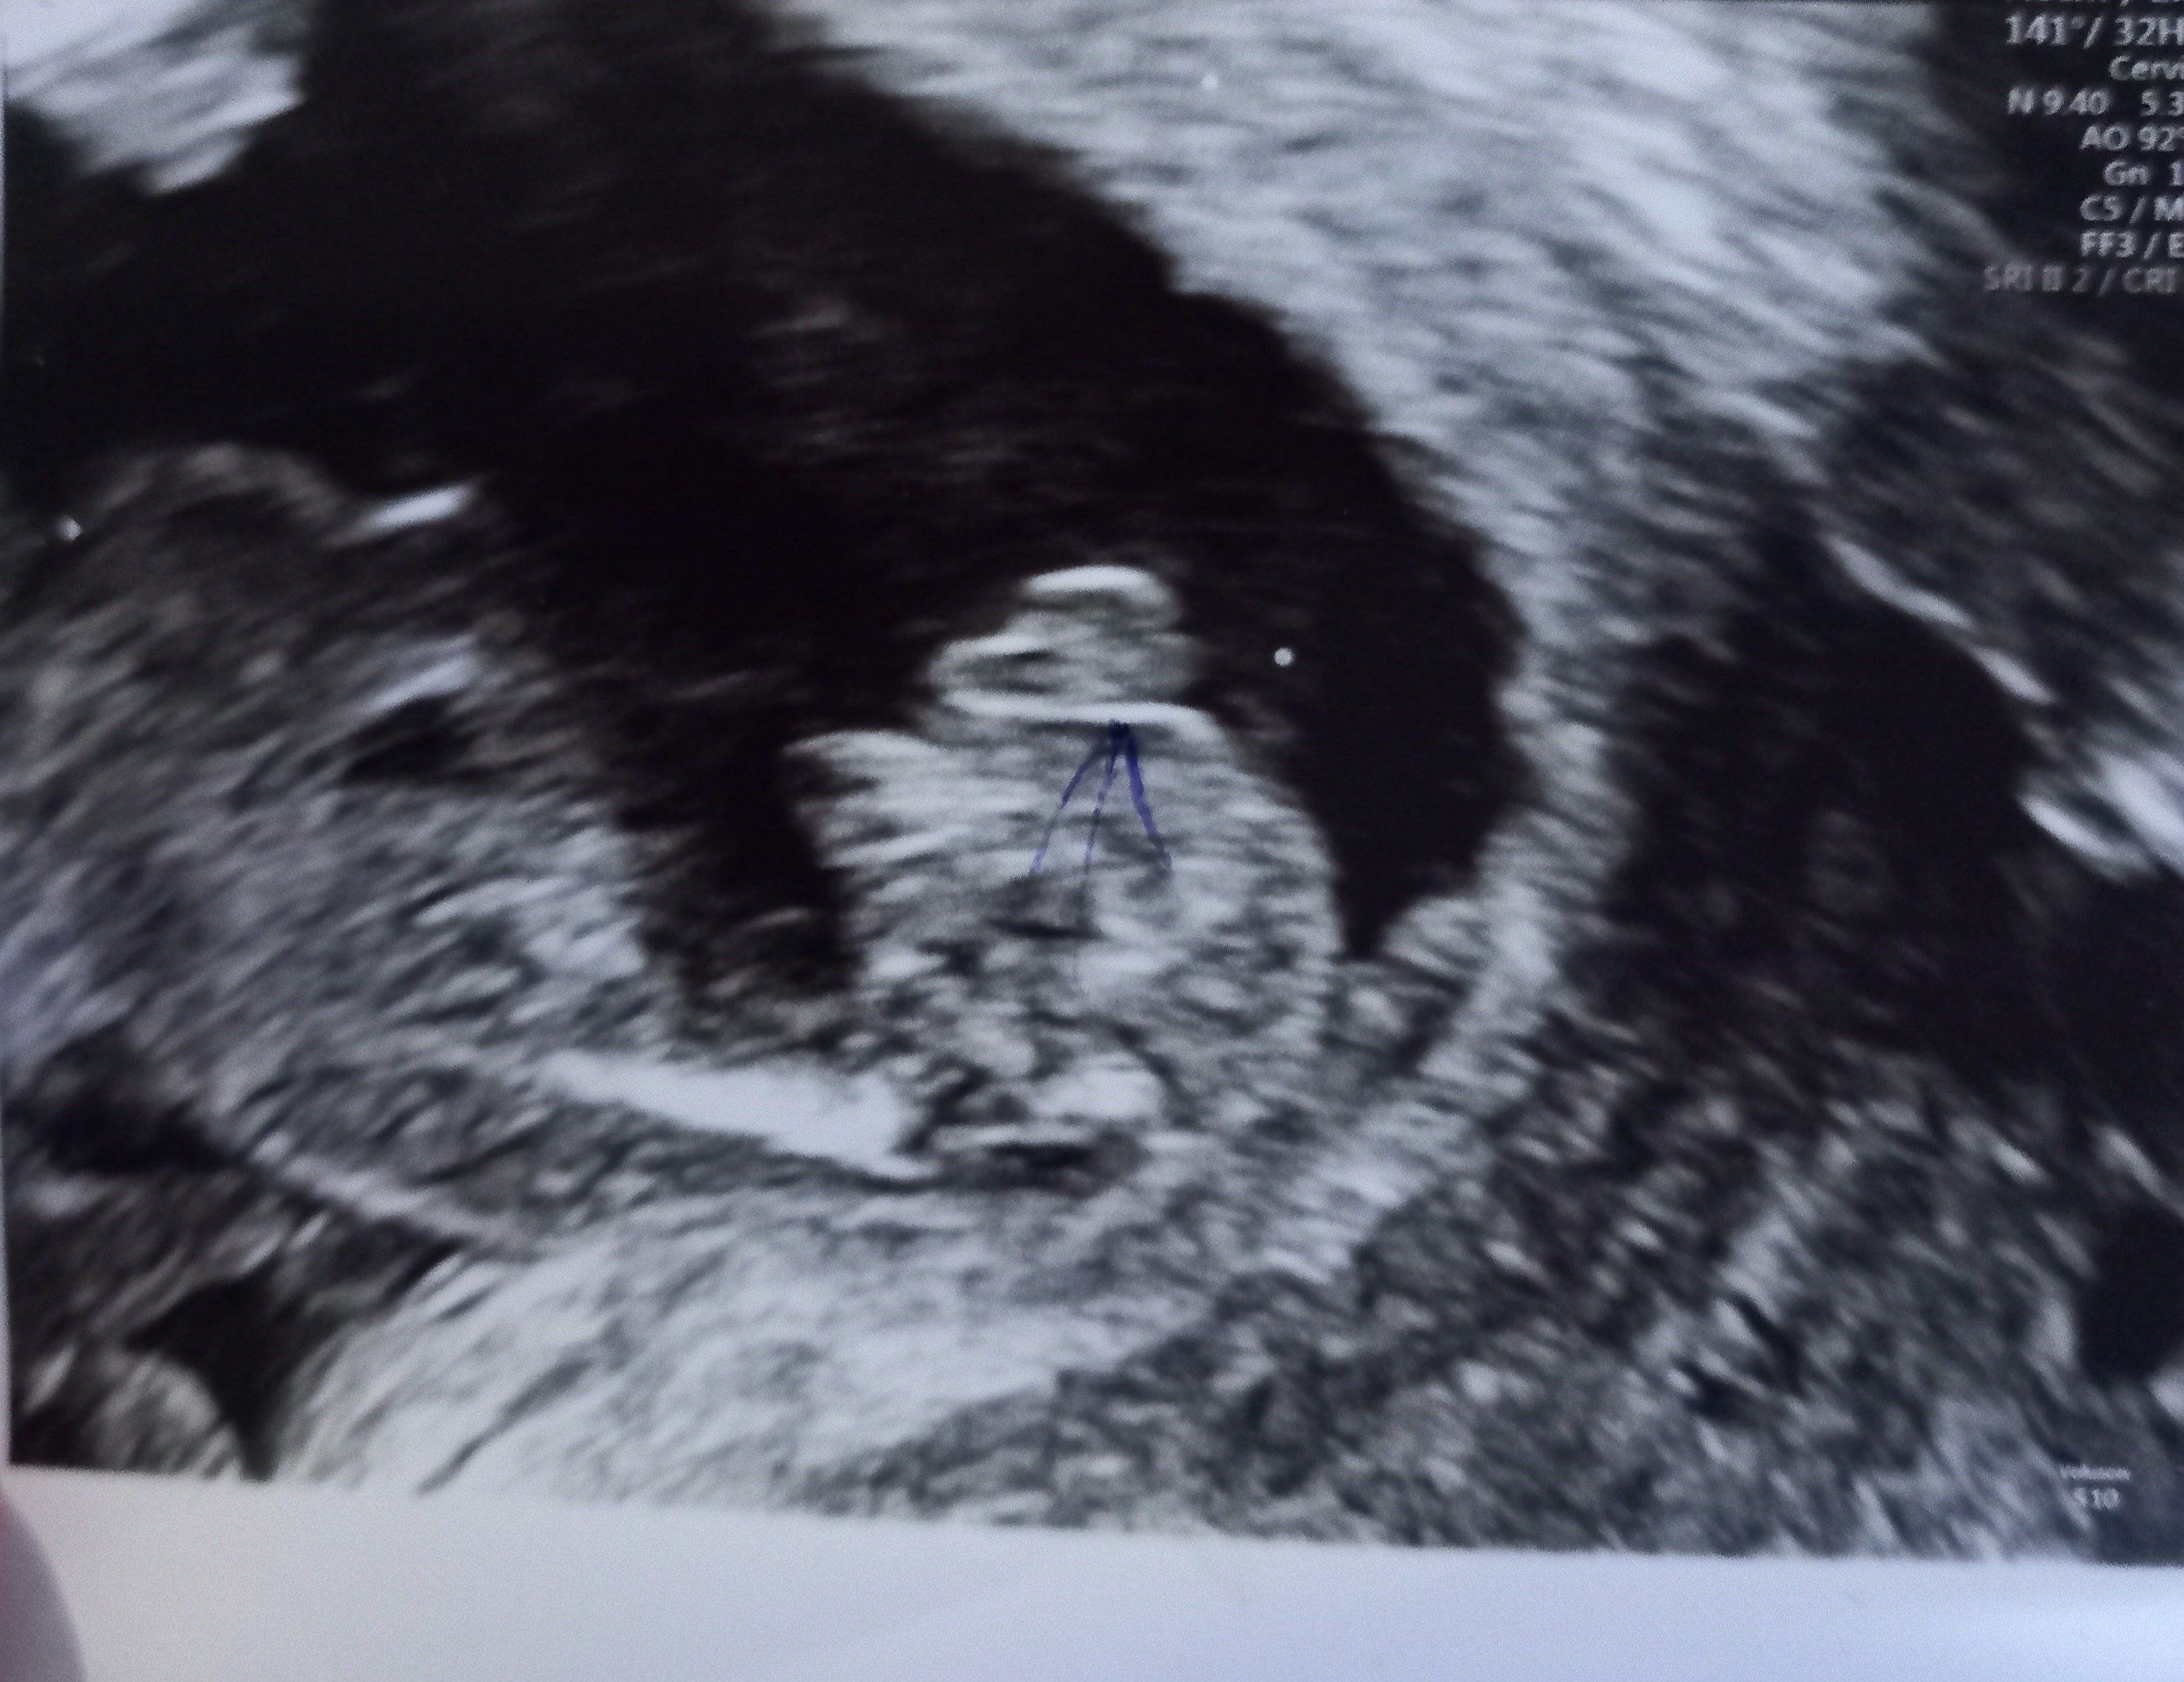

TutajDziewczyny a co myślicie o tym zdjęciu? Na początku lekarze mówili że będzie chłopczyk, a wczoraj lekarz powiedział, że to dziewczynka.

Faktycznie bardziej dziewczynka ale i z takich „dziewczynek” robili się chłopcy![]()